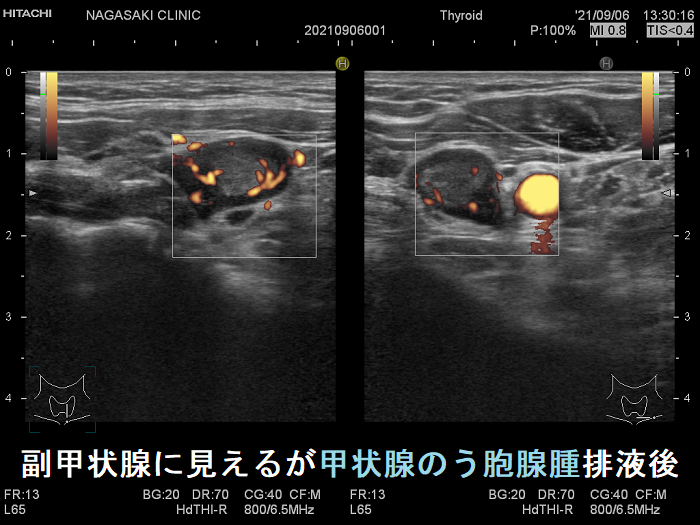

副甲状腺腺腫のように見えるも、実は排液後の甲状腺のう胞腺腫(甲状腺嚢胞腺腫)

副甲状腺腺腫と同じような位置(写真では甲状腺左葉の下極)にあり、副甲状腺腺腫のように見えるも、実は排液後縮小した甲状腺のう胞腺腫(甲状腺嚢胞腺腫)です。

最初から、その場所に甲状腺のう胞腺腫(甲状腺嚢胞腺腫)があったことを知っていれば何の問題も無いのですが。

下の写真を見て分かる通り、副甲状腺腺腫と鑑別が付きません。

副甲状腺に見えるが排液後縮小した甲状腺のう胞腺腫(甲状腺嚢胞腺腫) 超音波(エコー)画像

副甲状腺に見えるが排液後縮小した甲状腺のう胞腺腫(甲状腺嚢胞腺腫) 超音波(エコー)画像 ドプラーモード